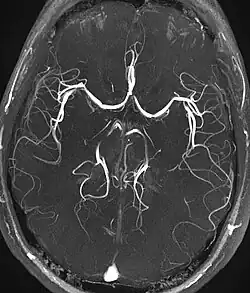

For magnetic resonance angiography (MRA), ToF is a major underlying method. In this method, blood entering the imaged area is not yet saturated, giving it a much higher signal when using short echo time and flow compensation. It can be used in the detection of aneurysm, stenosis or dissection.[5]